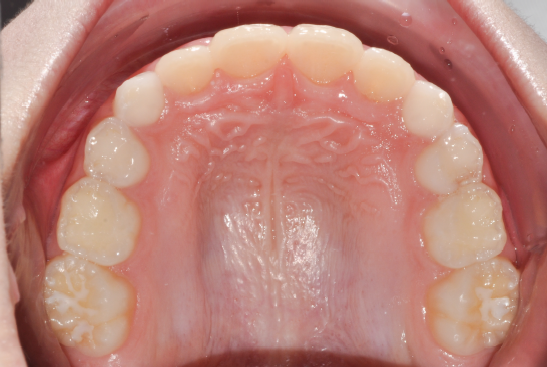

The patient presented with a skeletal Class I relationship and a mesofacial growth pattern, indicating balanced sagittal and vertical skeletal proportions. Dental examination revealed a Class I molar and canine relationship bilaterally. The patient was in the mixed dentition phase. Significant dental crowding was observed in both arches, consistent with a dentoalveolar discrepancy. Midline deviations were present, affecting dental symmetry and occlusal harmony. The maxillary lateral incisors were in crossbite, contributing to anterior transverse discrepancy and functional imbalance.

The orthodontic treatment plan was designed to address dentoalveolar crowding, transverse discrepancies, and midline deviations, while maintaining optimal periodontal health and achieving stable Class I molar and canine relationships. Specific objectives included correction of anterior crossbite, expansion and coordination of the arches, derotation of upper molars, preservation of incisor inclinations, derotation of lower posterior teeth with lingual root torque, leveling of the curve of Spee through incisor intrusion and controlled extrusion of deciduous teeth, and normalization of incisor inclinations. A clear aligner–based approach was selected to allow precise, controlled tooth movement, with particular